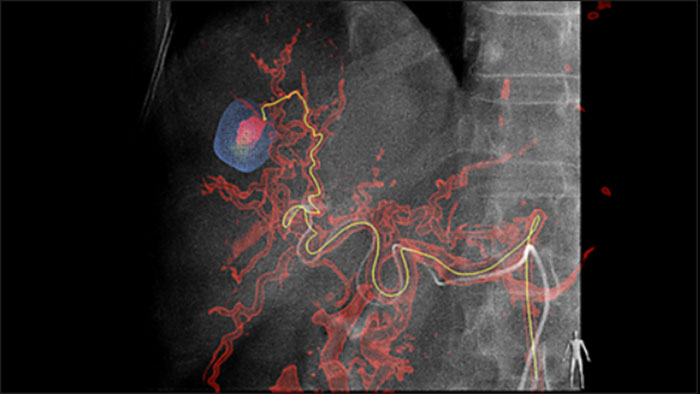

La solution de détection automatique des vaisseaux nourriciers améliore de manière significative la détection des artères nourricières. EmboGuide vous aide à maximiser l’efficacité de vos procédures de chimio-embolisation transartérielle en améliorant votre sensibilité, en réduisant les faux positifs et en optimisant la concordance entre les lecteurs1. EmboGuide fournit également un guidage 3D en temps réel efficace, basé sur le processus de travail, avec détection automatique des artères nourricières.1.

L’adoption de techniques de chimio/radioembolisation telles que la chimio-embolisation transartérielle et SIRT entraîne un besoin de standardisation et d’efficacité. Cas après cas, vous devez localiser de manière fiable et cohérente la ou les tumeurs, identifier tous les vaisseaux nourriciers et planifier/exécuter l’approche interventionnelle appropriée. Notre solution de détection automatique des vaisseaux nourriciers améliore de manière significative la détection des artères nourricières par rapport à l’utilisation de la tomographie à faisceau conique seule. EmboGuide vous aide à maximiser l’efficacité de vos procédures de chimio-embolisation transartérielle en améliorant votre sensibilité, en réduisant les faux positifs et en maximisant la concordance entre les lecteurs .1

La capacité de détecter et de différencier les nodules hépatiques et d’identifier les minuscules vaisseaux nourriciers est essentielle pour déterminer le traitement approprié. La navigation vers la région d’intérêt en atteignant tous les vaisseaux nourriciers, tout en restant sélective par rapport à la lésion, augmente les chances de succès. La confirmation de la fin et du succès du traitement alors que le patient est encore sur la table renforce la confiance dans les résultats cliniques.